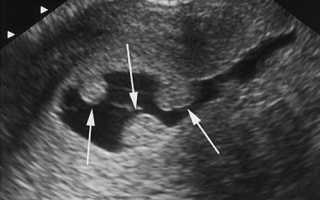

2. Вариантом нормы является и беременность — при этом в полости матки обнаруживается прикрепленное плодное яйцо. Минимальное количество ультразвуковых обследований при беременности — три.

Изображение матки на экране УЗИ

С помощью УЗИ малого таза можно увидеть многие патологии — например, миому матки

УЗИ органов малого таза оказывает помощь и при диагностике беременности. Уже с 3-4 недели плодное яйцо можно увидеть в полости матки и вне ее пределов. Особенную помощь УЗИ этого типа оказывает и при своевременном выявлении внематочной беременности.